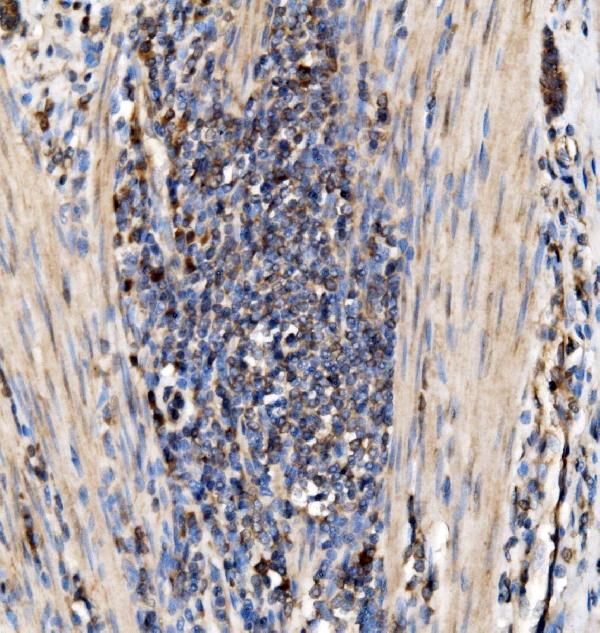

(Figure 3. IHC analysis of RPL10 using anti-RPL10 antibody (AAA126364).RPL10 was detected in a paraffin-embedded section of human stomach cancer tissue. Heat mediated antigen retrieval was performed in EDTA buffer (pH 8.0, epitope retrieval solution). The tissue section was blocked with 10% goat serum. The tissue section was then incubated with 2 ug/ml rabbit anti-RPL10 Antibody (AAA126364) overnight at 4 degree C. Biotinylated goat anti-rabbit IgG was used as secondary antibody and incubated for 30 minutes at 37 degree C. The tissue section was developed using Strepavidin-Biotin-Complex (SABC) with DAB as the chromogen.)

IHC (Immunohistochemisry)